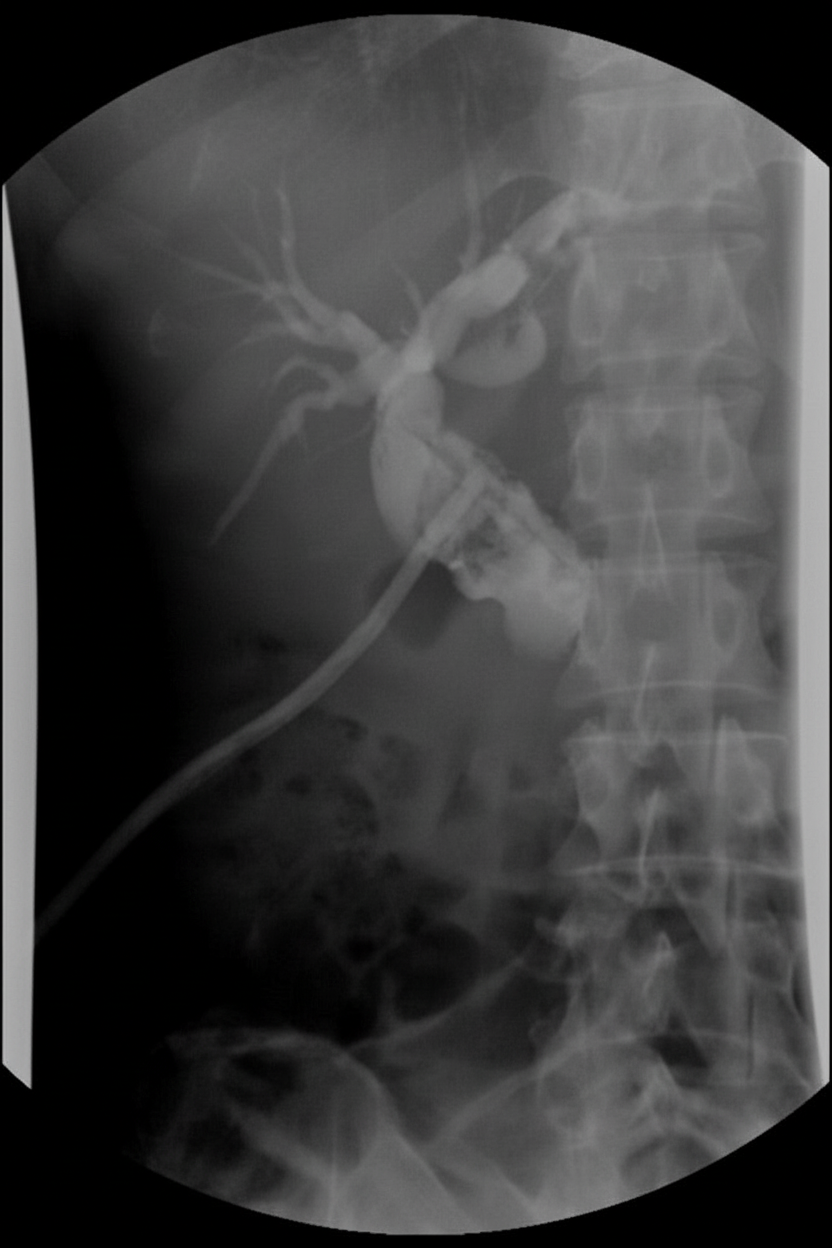

A patient with cholangitis underwent surgical intervention. The investigation shown in the post-operative period on the 10th day is:

Explanation: ***T-tube cholangiogram*** - Performed on **post-operative day 10** to assess **biliary tree patency** and check for **residual stones** before T-tube removal. - The **T-tube** is placed during **choledochotomy** in cholangitis surgery, and contrast is injected through it to visualize the biliary system. *ERCP* - **Endoscopic retrograde cholangiopancreatography** is typically a **therapeutic procedure** used pre-operatively or for complications. - Not routinely performed on **POD 10** as a post-operative investigation after T-tube placement. *MRCP* - **Magnetic resonance cholangiopancreatography** is a **non-invasive imaging** modality that doesn't require contrast injection. - Cannot be performed through a **T-tube** and is not the standard investigation shown on POD 10. *PTC* - **Percutaneous transhepatic cholangiography** involves **needle puncture** through the liver to access bile ducts. - Not indicated on **POD 10** when a **T-tube is already in place** providing direct biliary access.